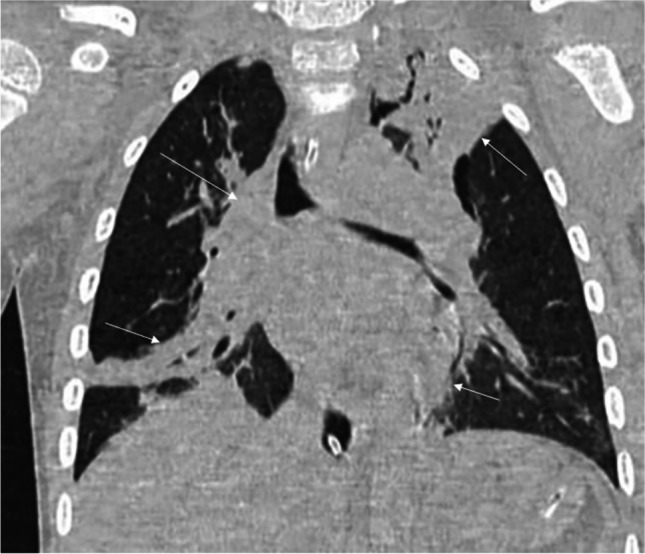

Tularemia pneumonia characteristically shows unilateral or bilateral lung consolidative opacities, hilar lymphadenopathy, and pleural effusion on chest radiography (Fig. 4). Chest CT often demonstrates dense lobar lung consolidation, usually in the periphery, and lymphadenopathy [48]. The complications of tularemia pneumonia include lung abscess and acute respiratory distress syndrome (ARDS) [48].

Fig. 4.

A posteroanterior chest radiograph in a 10-year-old boy with fever, cough, and malaise shows right hilar lymphadenopathy (thick arrow) and slight opacification within the right lower lung lobe (thin arrow). Ultrasonography (not shown) showed a small uncomplicated pleural effusion. Microbiological investigations confirmed tularemia